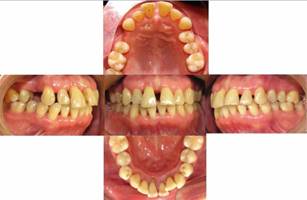

Paciente género femenino, 64 años, sin antecedentes médicos. Tratada entre los años 2010 y 2020. Su motivo de consulta en FOUCH es que sus dientes anterosuperiores se han ido separando y uno de ellos lo ve más “largo y suelto”. Relata que había recibido TP recientemente, donde se le había sugerido realizar la exodoncia de diente 1.1 y su reemplazo por un implante dental. La paciente deseaba un tratamiento que considerara corregir la malposición dental y la mantención de su dentición. Al examen periodontal se observa pérdida de inserción periodontal generalizada y MDP en sextante 2 y 5 (Figura 1). Se realiza periodontograma inicial (Figura 2a), en el cual se pesquisa un 66% de sitios con biofilm dental, sangrado al sondaje de 43%, múltiples recesiones gingivales y una pérdida del nivel de inserción clínica (NIC) en promedio de 3,7 mm. maxilar y mandibular. Los dientes más comprometidos presentaban un NIC de 9 mm. en incisivos. Se observó lesión de furca clase I en molares, supuración en los dientes 1.1 y 2.1 y movilidad grado 1, 2 ó 3 en todos los dientes presentes.